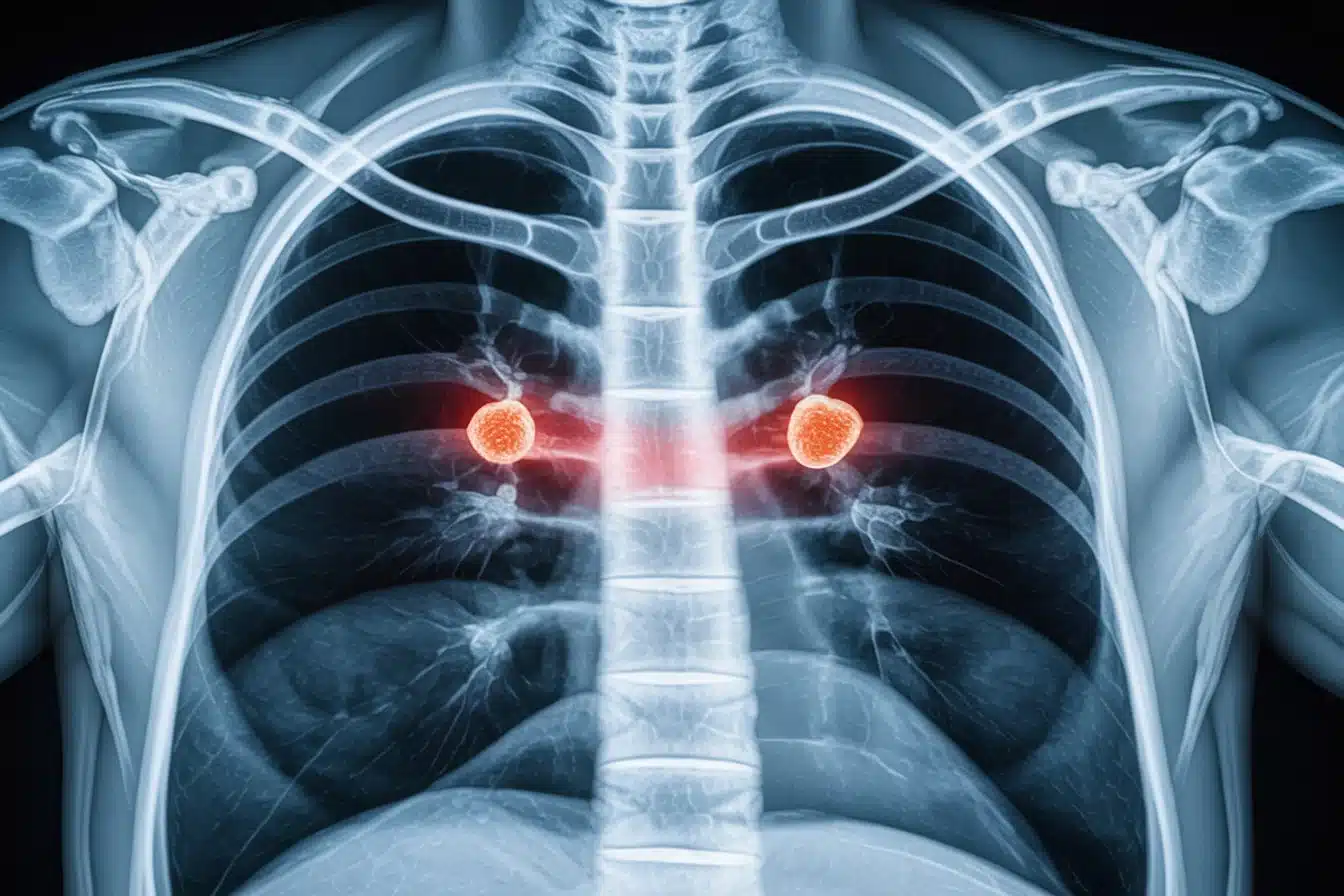

Nodules bénins versus nodules cancéreux

Les nodules pulmonaires se divisent en deux catégories : bénins et cancéreux. La majorité des nodules sont bénins, souvent dus à des cicatrices d’infections antérieures. L’exposition au tabac et à certaines toxines augmente le risque de développer un cancer. Les nodules malins peuvent indiquer un cancer primaire du poumon ou des métastases provenant d’autres organes.

Pour comprendre la nature exacte des nodules détectés, une évaluation médicale approfondie est essentielle. Des examens comme les tomodensitogrammes permettent d’analyser leur taille et leur forme. Un suivi régulier est crucial pour repérer toute évolution préoccupante, car certains nodules peuvent nécessiter une intervention si des changements surviennent avec le temps.